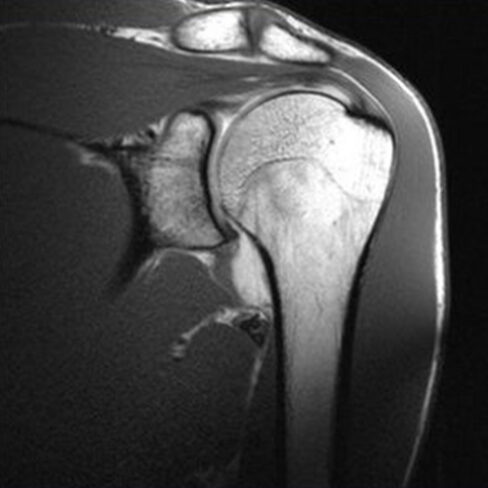

Czasem masz problemy z oceną stawów?

A może na co dzień zajmujesz się układem mięśniowo-szkieletowym?